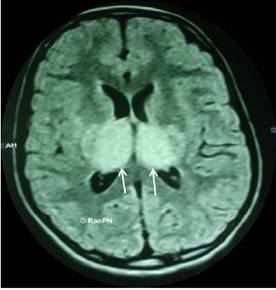

Nếu chỉ có một mẫu huyết thanh, thì hiệu giá kháng thể cao hơn 1/320 mới được xem là dương tính. Hiện nay phản ứng thường được dùng là phản ứng MAC ELISA. Phản ứng MAC ELISA: (IgM antibody capture enzyme linked immunosorbent assay): tìm kháng thể IgM, là kháng thể nói lên một nhiễm trùng mới mắc. Phản ứng này giữ vai trò quan trọng trong chẩn đoán và nghiên cứu dịch tễ học các bệnh nhiễm trùng vì kỹ thuật đơn giản và ít tốn kém. Nói chung các phản ứng huyết thanh đều có độ nhạy cao, nhưng độ đặc hiệu lại kém vì có phản ứng chéo với các giòng Flavivirus, nhất là tại những nơi có bệnh sốt Dengue, sốt xuất huyết hoặc Flavi khác lưu hành. Ngoài biện pháp phân lập virút trên các bệnh phẩm, hiện nay kỹ thuật MAC ELISA được sử dụng tìm IgM đặc hiệu trong dịch não tủy để xác định bệnh viêm não Nhật Bản trên các bệnh phẩm, hiện nay kỹ thuật MAC ELISA được sử dụng tìm IgM đặc hiệu trong dịch não tủy để xác định bệnh viêm não Nhật Bản. Phản ứng này có độ nhạy 75% trong giai đoạn cấp, trên 95% trong giai đoạn đang hồi phục, với độ chính xác > 95%. Kỹ thuật khuyếch đại gien (Polymerase Chain Reaction - PCR) là phương pháp nhân RNA của virút trong các bệnh phẩm như dịch não tủy, máu, mẫu não và tủy sống. Có thể là công cụ chẩn đoán nhiều hứa hẹn trong tương lai. Trong giai đoạn cấp thường thấy điện não đồ hoạt động sóng nhọn, gai chậm hoặc nhiều gai xen lẫn với những hoạt động chậm. Trong giai đoạn bán cấp hầu hết các trường hợp đều có sóng chậm lan tỏa ở cả hai bán cầu và có xu hướng ưu thế ở một bên. | Hình ảnh chụp CT scan não bệnh nhân viêm não Nhật Bản |

Chụp cắt lớp điện toán (CT scan - computerized tomography), cộng hưởng từ (MRI - magnetic resonnance imaging). Kết quả 50% chụp cắt lớp điện toán ở bệnh VNNB có hình ảnh giảm tỷ trọng ở một hay nhiều chỗ ở những vùng đồi thị, nhân xám nền sọ, não giữa, cầu não, hành tủy. Hình ảnh cộng hưởng từ thường rõ và nhạy hơn, cho thấy có tổn thương lan tỏa, ở hai bán cầu não, tiểu não, và có hình ảnh của xuất huyết tại đồi thị.